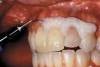

The whitening agents are available in various concentrations ranging from 10% carbamide peroxide (equal to 3.4% hydrogen peroxide) to 38% hydrogen peroxide. If the higher concentration agents contact the soft tissues, they can produce a chemical “burn” that turns the tissues temporarily white (Figure 1 and Figure 2). Although tissues quickly return to their normal color once they rehydrate, they may be mildly uncomfortable for a few hours. The patient may be distressed by the temporary appearance of the whitened soft tissues. A rubber dam or other protective barrier is mandatory to effectively seal off the tissues (Figure 3). In-office systems usually supply a light-cured resin in a syringe to apply around the cervical areas to confine the agent to the teeth (Figure 4 and Figure 5). In addition, flexible spreaders should be placed in the mouth to prevent the cheeks or lips from contacting the whitening agent.

Figure 4  Manufacturer’s light-cured resin material syringed into the soft tissue to ensure proper isolation.

Figure 5  Manufacturer’s light-cured resin material syringed into the soft tissue to ensure proper isolation.